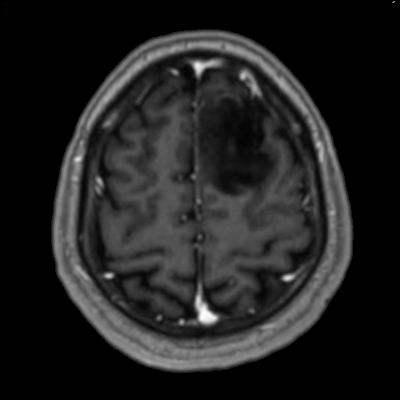

- Sol frontal kortikal-subkortikal yerleşimli aksiyel T2A görüntüde hiperintens sinyal özelliği gösteren (oklar) ve FLAIR görüntüde sinyali ağırlıklı olarak baskılanan (oklar) kitlesel lezyon izleniyor. Lezyon T1A görüntüde hipointens olup post-kontrast T1A görüntüde bu düzeyde patolojik kontrastlanma izlenmiyor (oklar).

- T1AG’de genellikle hipointens, T2AG’de ise genellikle homojen hiperintens görünümde ve kitle etkisi hafif-orta düzeydedir.Ödem genellikle eşlik etmez ya da minimal düzeydedir.

- FLAIR’de T2’ye benzer şekilde hiperintens görünür. Ancak T2–FLAIR mismatch bulgusu, bu tümör tipi için oldukça karakteristiktir.

- Grade 2 ve 3 tümörlerde çoğunlukla kontrast tutulumu yoktur veya minimal düzeydedir. Grade 4 IDH-mutant astrositomlarda, nekroz veya mikrovasküler proliferasyon varsa heterojen kontrast tutulum gözlenebilir. Kontrast tutulumu her zaman malignite derecesini yansıtmayabilir; bu nedenle biyopsi ve moleküler analiz mutlaka gereklidir.